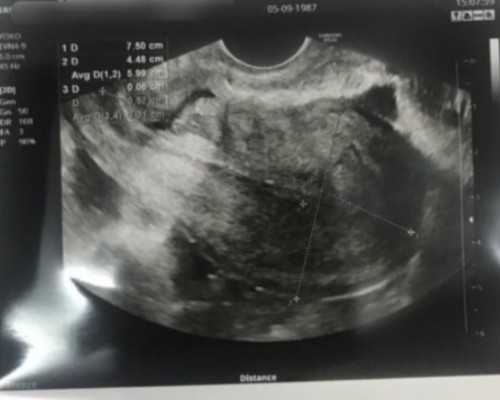

妇婴三代医院试管婴儿成功案例 妇婴三代医院试管中心自成立以来,已成功帮助众多患者圆了生育梦。例如,李女士在妇婴医院接受了第三代试管婴儿手术后,成功怀孕并生下了一个健康的宝宝。